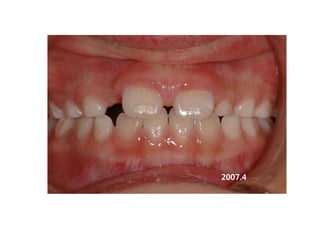

2007.4

2008.02.27.3y2m